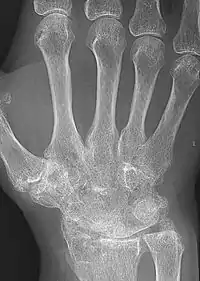

X-rays of the hands and feet are generally performed when many joints affected. In RA, there may be no changes in the early stages of the disease or the x-ray may show osteopenia near the joint, soft tissue swelling, and a smaller than normal joint space. As the disease advances, there may be bony erosions and subluxation. Other medical imaging techniques such as magnetic resonance imaging (MRI) and ultrasound are also used in RA.[20][67]